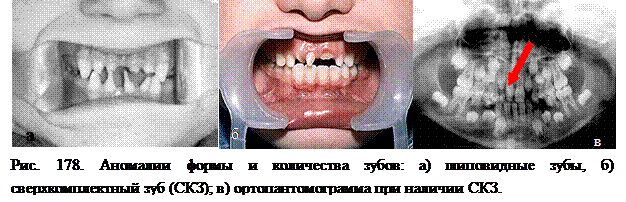

Бывают уродливые зубы с чрезмерно большими коронками или мелкие, щиповидные, рудиментарной формы.